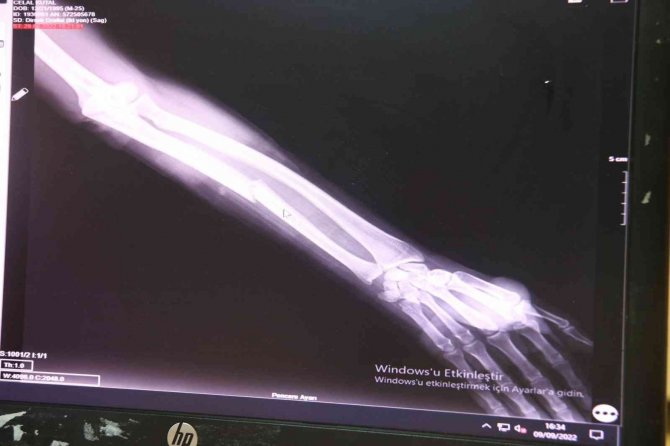

Kazalarda sadece sürücülerin yaralanmadığını, yayaya çarpmalardan kaynaklı beyin kanaması ve kalıcı hasarın olduğu ağır vakalar oluştuğunu belirten Dr. Mehmet Özel, gebe ve yaşlılarda kırık ve travma ihtimalinin daha yüksek olduğunu aktardı. Dr. Özel, "Hastaneye başvurularda özellikle en çok rastladığımız şey olarak yaş grubu diye ayırsak çocuk yaşlarından tutun yetişkin, yaşlılar hatta gebeler bile bu grup içerisinde. Çünkü sadece dediğim gibi sürücü değil, yolcu veya yaya yürüyene çarpmasından dolayı ya da bir başka bir ulaşım arasına çarpmasından dolayı kazalar oluyor. Giden bir cismi aniden durduğunda ya da düştüğünde koruyucu bir ekipman veya başka bir şey olmadığından dolayı direkt tramvaya açık olduğu için baş boyun ve yüz yaralanmaları çok sık görülüyor. Baş boyun yüz yaralanmaları derken bu basit bir sıyrık yüzde bir kesiden tutun da yüz kemiklerini, kafatası kemiklerini kırıklara, beyin kanamasına kadar neden olabiliyor. Bu hasta gruplarında hastalar yoğun bakıma yatıyor. Ameliyata girmek zorunda kalıyorlar. Kalıcı sakatlıklar doğabiliyor, çok büyük sıkıntılar oluyor. Onun dışında ikincil olarak bizim uzuv dediğimiz bu ön kol, bacak bu tarz ekstremite yaralanmaları da olabiliyor. Bu yaralanmalarda en çok el bilek, ayak bileği düzeyinde kırıklar oluyor. Bunlar basit atele de taburcu da edilebiliyor. Ama dirsek işte ön kol dediğimiz veya kalça bölgesi dediğimiz kırıklarında ciddi ameliyat olması gerekiyor hastanın ve uzun dönemde sakat da kalabiliyor. Hastalar karaciğer, dalak yaralanmasıyla, aynı zamanda akciğer zedelenmesi, sönmesiyle de gelebiliyor. Bizim Acil Tıp olarak ayaktan tedavi edip taburcu ettiğimiz hasta grubu olmakla beraber hastaneye yatışını yaptığımız, yoğun bakımda takip ettiğimiz ve ameliyat için ameliyathaneye gönderdiğimiz hasta grubu da oluyor" dedi.